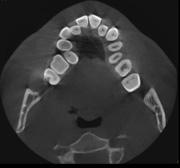

En los cortes tomográficos en la Figura 6 se muestra el colapso maxilar severo en la Figura 7 y mandibular severo con el tratamiento de conducto en el OD 36.

Figura 6. Corte axial maxilar. Figura 7. Corte axial mandibula. Figura 8. Frente. Figura 9. Clase III molar bilateral.